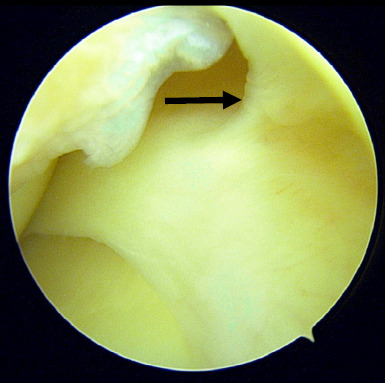

This report presents the case of an 18-year-old female student with a low BMI, who was otherwise healthy. She presented with chronic anterior right knee pain persisting for 1 year. The pain began spontaneously and gradually increased in severity, especially during long distance walking and standing for more than 15 minutes. The symptoms did not subside with medication and physiotherapy. All biochemical and radiological investigations to rule out other related possible aetiologies were unremarkable. The patient eventually underwent an arthroscopic knee surgery, during which the intraoperative findings revealed the Hoffa fat pad over the anteromedial knee joint. This was debrided and after surgery, she was symptom free and had resumed her normal activities.

Abstract Image